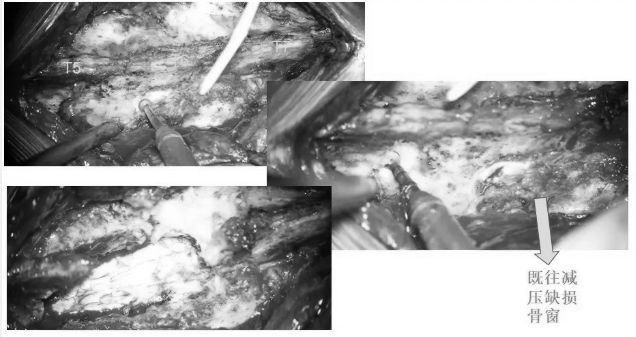

▼取下部分T5、T6椎板

▼术中超声显示髓内海绵状血管瘤超出骨窗大小,向T7方向生长,继续磨除部分T7椎板,扩大暴露范围

▼沿后正中切开,即可见含铁血黄素沉积带及陈旧性血凝块

▼用细致的双较或者剥离子沿含铁血黄素沉积带,分离海绵状血管瘤并电凝切断供血分支血管

▼逐步显露血管瘤腹侧面

▼血管瘤完整取出

▼测量瘤腔大小,明确肿瘤全切

▼用Proline缝线间断缝合软脊膜,封闭瘤腔,水密缝合硬脊膜